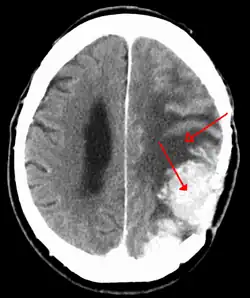

An MRI of the brain, demonstrating the appearance of a meningioma

Meningiomas are visualized readily with contrast CT, MRI with gadolinium,[23] and arteriography, all attributed to the fact that meningiomas are extra-axial and vascularized. CSF protein levels are usually found to be elevated when lumbar puncture is used to obtain spinal fluid. On T1-weighted contrast-enhanced MRI, they may show a typical dural tail sign absent in some rare forms of meningiomas.[18]